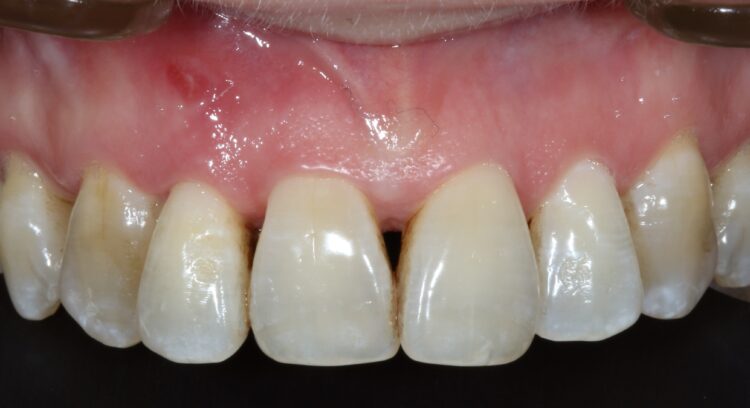

Three months later a small crestal incision was performed to expose and remove the healing cap and impressions taken to construct an under-contoured screw-retained provisional crown. Over a period of two visits, composite was incrementally added to the subgingival portion of the temporary crown to expand and modify the soft tissue emergence profile until an acceptable shape was achieved.

A new impression was taken capturing the NEW transmucosal shape and a customised abutment and zirconia crown were fabricated as a one-piece screw-retained restoration and fitted to complete the case.

A three-year review of the final outcome displayed adequate hard and soft tissue volume with complete papilla infill and a pleasing outcome for the patient.